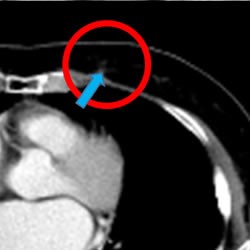

治疗前摄影图CT (治疗前:CT)

开始治疗后70日后(2个月半)(治疗 70天后)

*肺癌, 纵隔镜 淋巴结转移(71 岁男性)

来自中国的一名患者. 1疗程 5回 PD-1免疫抗癌剂(抗PD-1抗癌剂)

并用 免疫疗法NK・T细胞疗法 肿瘤减少了一半以上.

目前.以彻底消除肿瘤为目标.进行第2疗程的治疗.